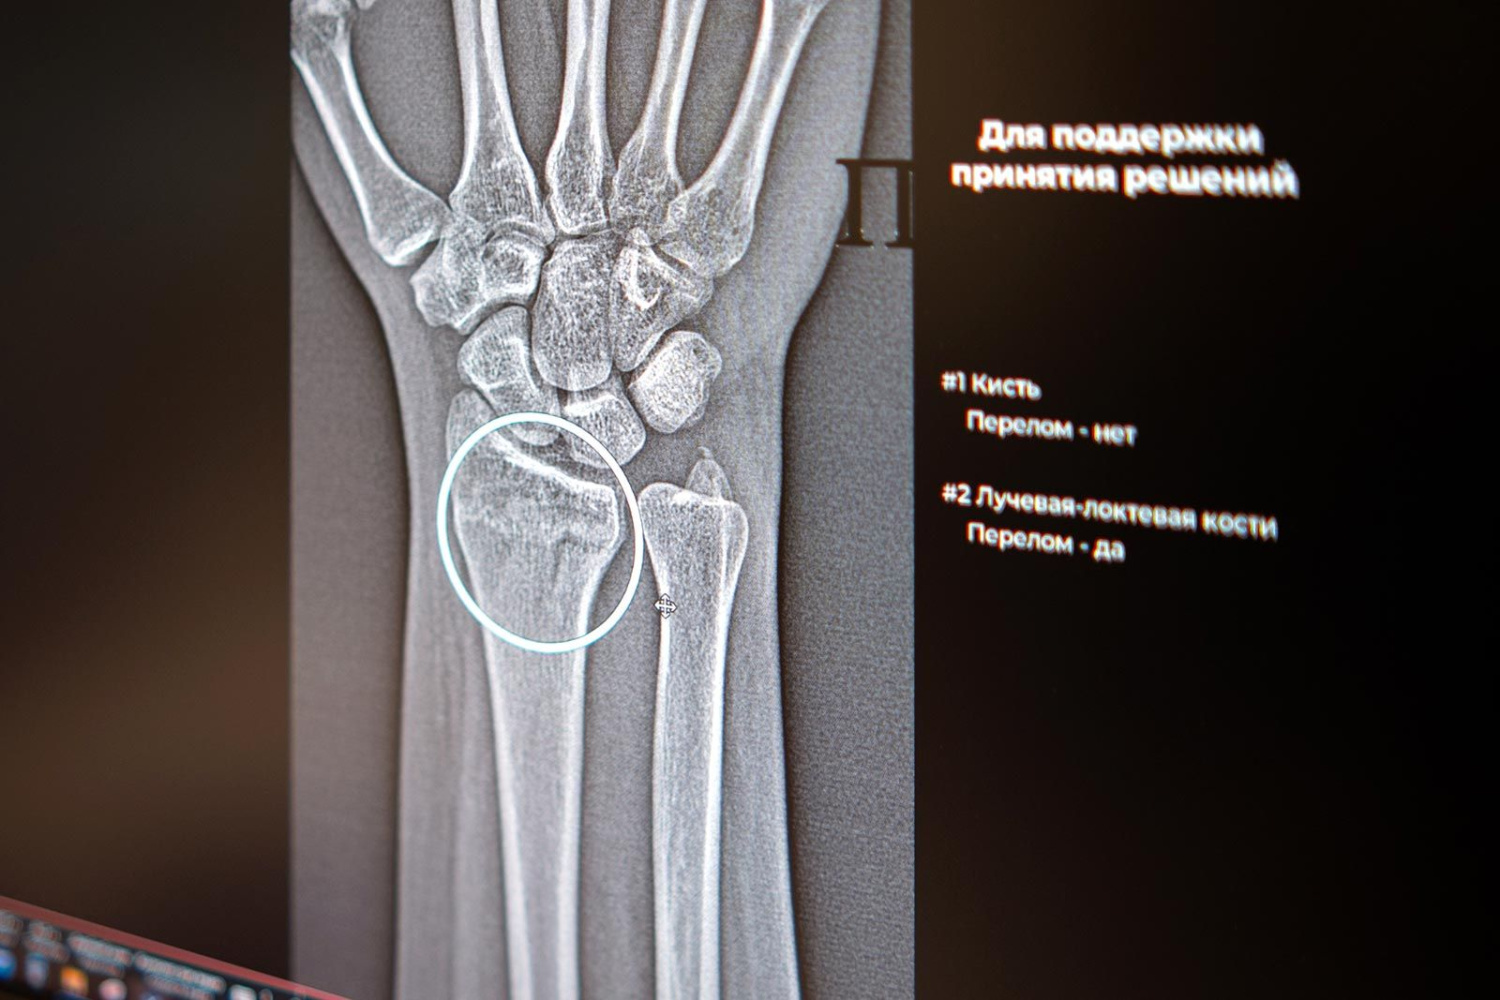

В Москве начали работать два новых сервиса на основе искусственного интеллекта для высокоточной диагностики множественных переломов голеностопного и лучезапястного суставов. Анастасия Ракова, заместитель мэра Москвы по вопросам социального развития, подчеркнула: «Сегодня в распоряжении московских рентгенологов уже более 60 ИИ‑сервисов. Одни отличают норму от проявления заболевания, другие, например, могут измерять границы и размеры патологии. Сервисы применяются по 43 клиническим направлениям. В условиях большого потока пациентов технологичные ассистенты помогают сохранять высокое качество и скорость диагностики».